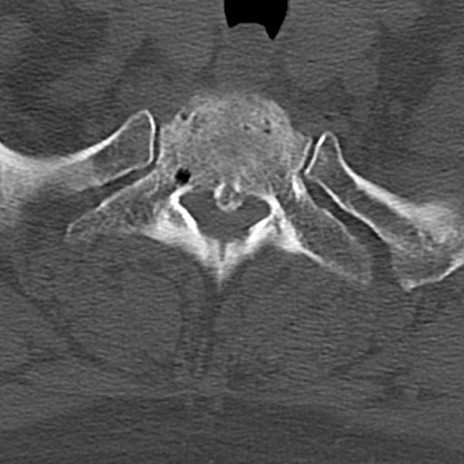

頚椎CT

横断像